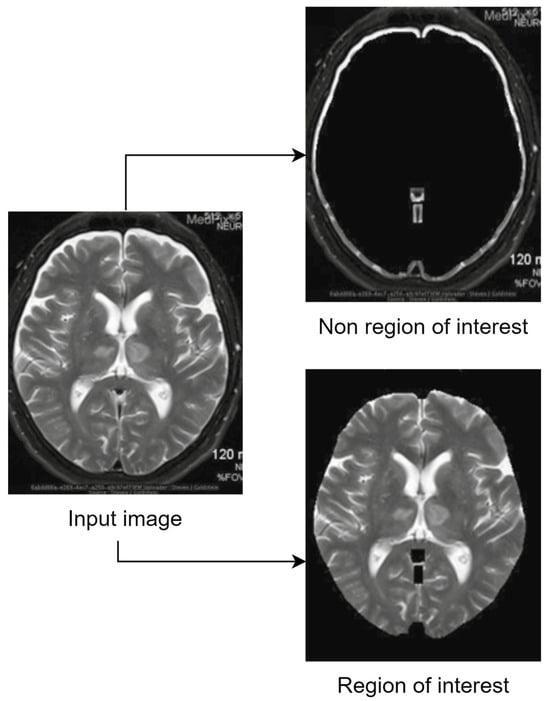

The term “region of interest” (ROI) refers to the area of a picture that is more significant than other areas [8], while non-ROI refers to the rest of the image. Applying lossy compression on non-ROI and lossless compression on ROI leads to maintaining the necessary diagnostic features of the medical image while achieving a high compression ratio. Utilizing ROI-based compression has the benefit of offering a high compression ratio without compromising the quality of a significant portion of the image [9]. Because an image’s compression ratio is strongly related to its ROI size (a smaller ROI means better CR), precisely defining the size and location of the diagnostic zone from medical pictures becomes very important. It is crucial to appropriately detect ROI, since it includes crucial diagnostic information that cannot be altered, and the CR of the image is dependent on its size. The detection of ROI is a vital task since incorrectly located ROI might result in the loss of diagnostic data in medical pictures. One of the first steps in any ROI-based compression technique is ROI selection. The complexity and execution duration of any approach are determined by how the ROI is chosen. Some common ROI-selection strategies (such as region growth and saliency maps) are employed frequently by different researchers, or sometimes the ROI is chosen manually if the images follow a certain pattern. After the regions are defined, different compression techniques are applied to preserve the region of interest and to save space by sacrificing the non-ROI. Usually, to reconstruct the input image, the inverted process is applied during the decompression step. Figure 1 shows the general process of ROI-based compression and highlights the main steps that are followed to achieve hybrid image compression. Of course, that extra steps such as filtering, salt and pepper noise reduction or image watermarking (used for authentication and tampering prevention) are to be expected.

The whole idea behind the ROI-based techniques can be graphically summarized in the example presented in Figure 2.

Another example of how the output of an ROI and RONI separation algorithm shall work is presented in Figure 3.